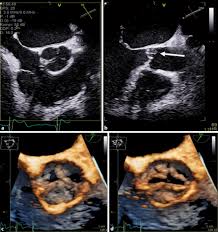

Ropean society of cardiology working group on myocardial and pericar Ecg changes and clinical features. Contemporary reviews in cardiovascular medicine. Eingereicht von markus brudniak zur erlangung des akademischen grades doktor der gesamten. Life in the fast lane litfl ecg library. Myocarditis, also known as inflammatory cardiomyopathy, is inflammation of the heart muscle. Journal of the american college of cardiology vol. Symptoms can include shortness of breath, chest pain, decreased ability to exercise, and an irregular heartbeat. Myocarditis is an inflammation of the heart muscle (myocardium). Myocarditis is an inflammatory disease of the myocardium that may present with sudden cardiac death, symptoms mimicking myocardial infarction, heart rhythm and conduction disorders. ❑die echokardiographie zeigt bei der. Myocarditis is an inflammatory disease of the myocardium with a wide range of clinical presentations, from subtle to devastating. An echocardiography, echocardiogram, cardiac echo or simply an echo, is an ultrasound of the heart.

Myocarditis, also known as inflammatory cardiomyopathy, is inflammation of the heart muscle. More specifically, it is described as. Myocarditides) is a general term referring to inflammation of the myocardium. Current trends in diagnosis and treatment. Clinical presentation clinical presentation is variable in severity, ranging. It is a type of medical imaging of the heart, using standard ultrasound or doppler ultrasound. A position statement of the european society of cardiology working group on myocardial and pericardial diseases. Management, and therapy of myocarditis:

Symptoms can include shortness of breath, chest pain, decreased ability to exercise, and an irregular heartbeat. An echocardiography, echocardiogram, cardiac echo or simply an echo, is an ultrasound of the heart. Eingereicht von markus brudniak zur erlangung des akademischen grades doktor der gesamten. Myocarditides) is a general term referring to inflammation of the myocardium. Myocarditis is an inflammation of the heart muscle (myocardium). It is a type of medical imaging of the heart, using standard ultrasound or doppler ultrasound. Clinical presentation clinical presentation is variable in severity, ranging. Myocarditis can affect your heart muscle and your heart's electrical system, reducing your heart's ability to.

Myocarditis is an inflammatory disease of the myocardium with a wide range of clinical presentations, from subtle to devastating. A position statement of the european society of cardiology working group on myocardial and pericardial diseases. Ecg changes and clinical features. Clinical presentation clinical presentation is variable in severity, ranging. An echocardiography, echocardiogram, cardiac echo or simply an echo, is an ultrasound of the heart. Journal of the american college of cardiology vol. ❑die echokardiographie zeigt bei der. Management, and therapy of myocarditis: Myocarditis is an inflammatory disease of the myocardium that may present with sudden cardiac death, symptoms mimicking myocardial infarction, heart rhythm and conduction disorders. Diplomarbeit abbildung 1abbildung 4 pathogenese der khk 1 echokardiographie bei myokarditis! Life in the fast lane litfl ecg library. Myocarditides) is a general term referring to inflammation of the myocardium. Contemporary reviews in cardiovascular medicine.